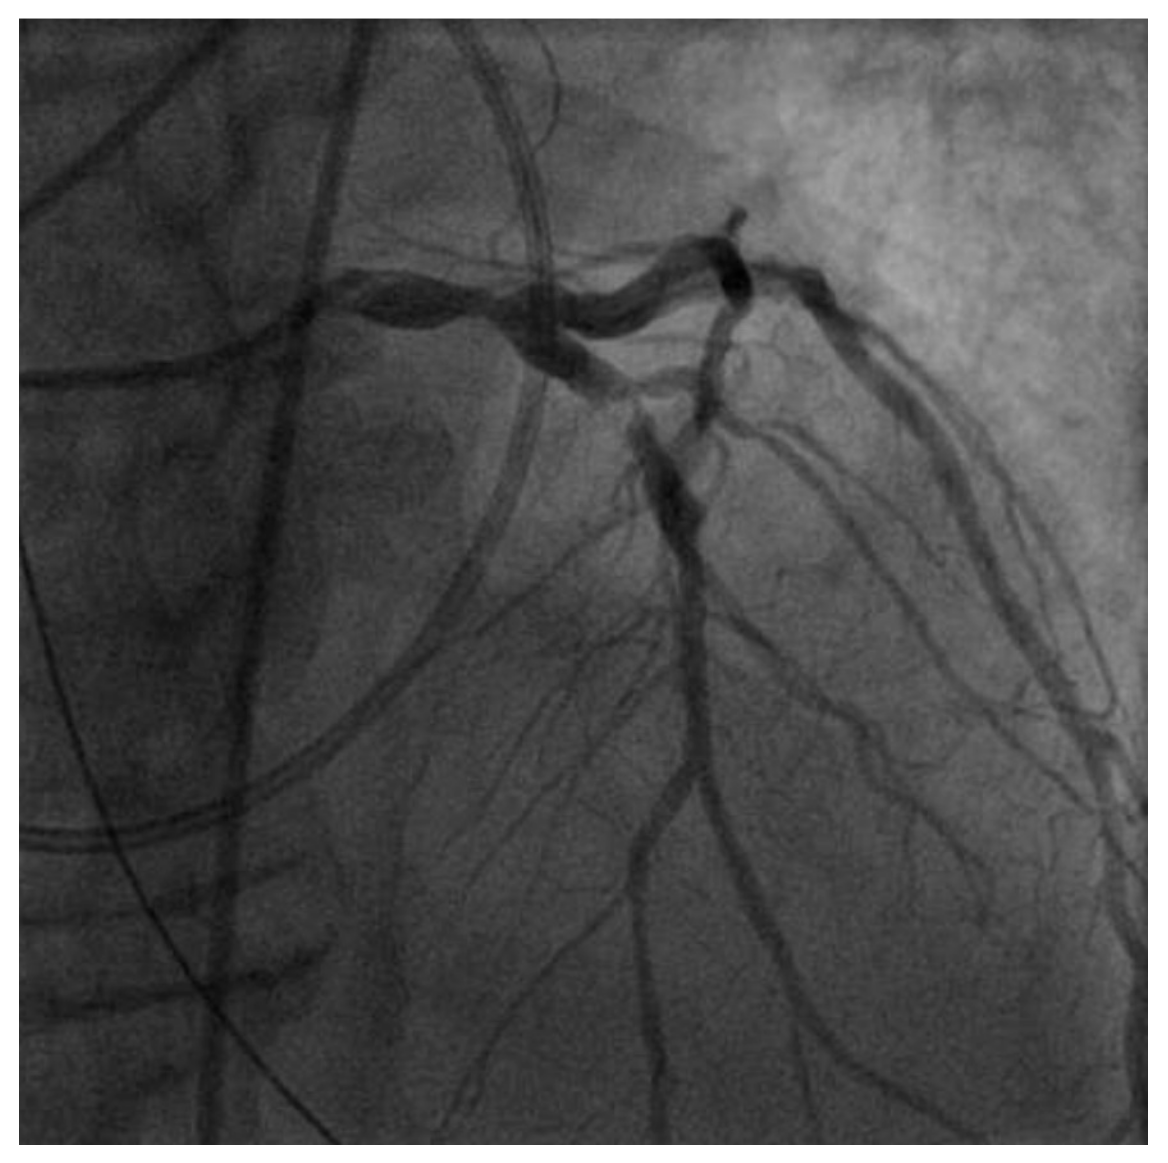

4. Investigations